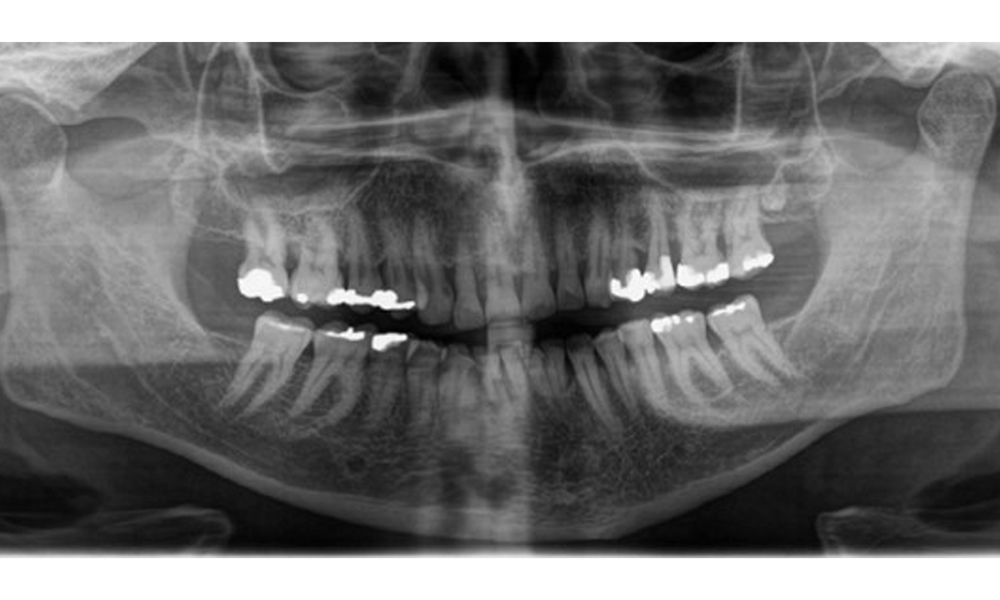

Aspecte radiologice

Se observă dentiție adultă completă, cu pierdere osoasă generalizată între 20-50% și zone multiple de pierdere osoasă verticală. Examenul radiologic nu a evidențiat carii vizibile. (Fig. 7)